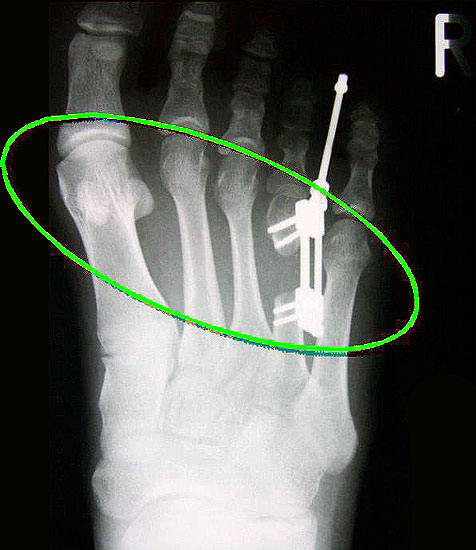

Das im Folgenden vorgestellte Operationsverfahren beschreibt die Kallusdistraktion von Metatarsalia nach den Prinzipien von Ilisarov 21 unter Verwendung eines internen, winkelstabilen Titan-Minifixateur (Klauser 2009). Der interne Distraktor ermöglicht während der Distraktions- und der Durchbauungsphase aufgrund seiner hohen Stabilität je nach Modell (18 mm, 23 mm) eine Verlängerung von bis zu 25 mm. Nach interner Anlage des Minifixateurs, meist lateral, kann über eine kontinuierliche Kallusdistraktion der Metatarsalebogen unter frühzeitiger Mobilisation im Gips oder Short-Walker rekonstruiert werden 15. Über einen interdigital und transcutan ausgeleiteten Aktivatorstab wird die Distraktion vom Patienten selber täglich morgens und abends durchgeführt. Zusätzlich vorliegende Strahlpathologien, wie zum Beispiel eine verkürzte Strecksehne oder ein kontraktes Metatarsophalangealgelenk können im Rahmen der Erstoperation ebenso therapiert werden wie z.B. ein Hallux valgus, ein Hallux valgus interphalangeus und/oder ein Digitus quintus varus (Klauser 2009). Nach Rekonstruktion des Metatarsalebogens wird in einem zweiten, kleinen Eingriff der Aktivatorstab über eine Spezialpinzette diskonnektiert und entfernt, wobei der Distraktor als interne Fixation belassen wird. Die Entfernung des Distraktors erfolgt in der Regel nach 9 – 12 Monaten, da es sich meist um angeborene kindliche Fehlbildungen handelt (Brachymetatarsie) und eine operative Intervention frühzeitig im Kindesalter erfolgen sollte (Klauser 2009).

Die Analyse der Ergebnisse zeigt, dass die Osteogenese beim Kind deutlich schneller und potenter verläuft als beim Erwachsenen. So war die knöcherne Durchbauung  nach Beendigung der Kallusdistraktion bei 8 – 12 jährigen Kindern fast immer nach 8-12 Wochen abgeschlossen und damit deutlich schneller als beim Erwachsenen. Hier werden in der Literatur über Konsolidierungszeiten von bis zu 3,8 Monate/cm berichtet 17. Festzustellen bleibt auch, dass die Kallusbildung bei Kindern (8 – 12 Jahre) am Fuss langsamer erfolgt als im Bereich der Metacarpalia, wo die durchgeführten Distraktionen unproblematisch verliefen und regelhaft bereits nach ca. 6 Wochen durchbaut waren 18

Meist kam ein 18mm Minifixateur zur Anwendung und ausnahmslos wurde er lateral am Metatarsale implantiert. Bis auf das Metatarsale 5 wurden vom Autor alle weiteren Metatarsalia (MT1 – MT4) isoliert oder kombiniert verlängert. In 7 Fällen wurde eine simultane Verlängerung zweier Metatarsalia (2x MT1 und MT4, 4x MT3 und MT4, 1x MT2 und MT3) vorgenommen. Bei einem Großteil der Patienten musste eine Strecksehnenverlängerung entweder im Rahmen der Erstoperation oder im Rahmen der Aktivatorentkopplung vorgenommen werden. In neun Fällen (ausnahmslos bei Erwachsenen > 30 Jahre) sogar 2x sowohl während des Erst- als auch Zweiteingriffes. Annähernd regelhaft sind bei den eben genannten Eingriffen Arthrolysen des Metatarsophalangealgelenks des betroffenen Zehenstrahls erforderlich, da durch die Distraktionsverlängerung eine hohe Kompression auf das jeweilige Grundgelenk entsteht.